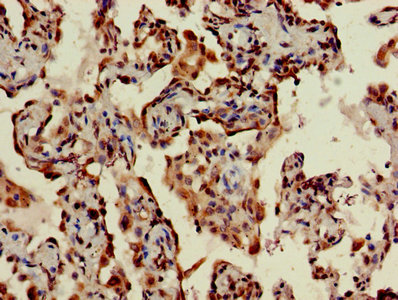

IHC image of CSB-PA023754LA01HU diluted at 1:400 and staining in paraffin-embedded human lung cancer performed on a Leica BondTM system. After dewaxing and hydration, antigen retrieval was mediated by high pressure in a citrate buffer (pH 6.0). Section was blocked with 10% normal goat serum 30min at RT. Then primary antibody (1% BSA) was incubated at 4°C overnight. The primary is detected by a biotinylated secondary antibody and visualized using an HRP conjugated SP system.